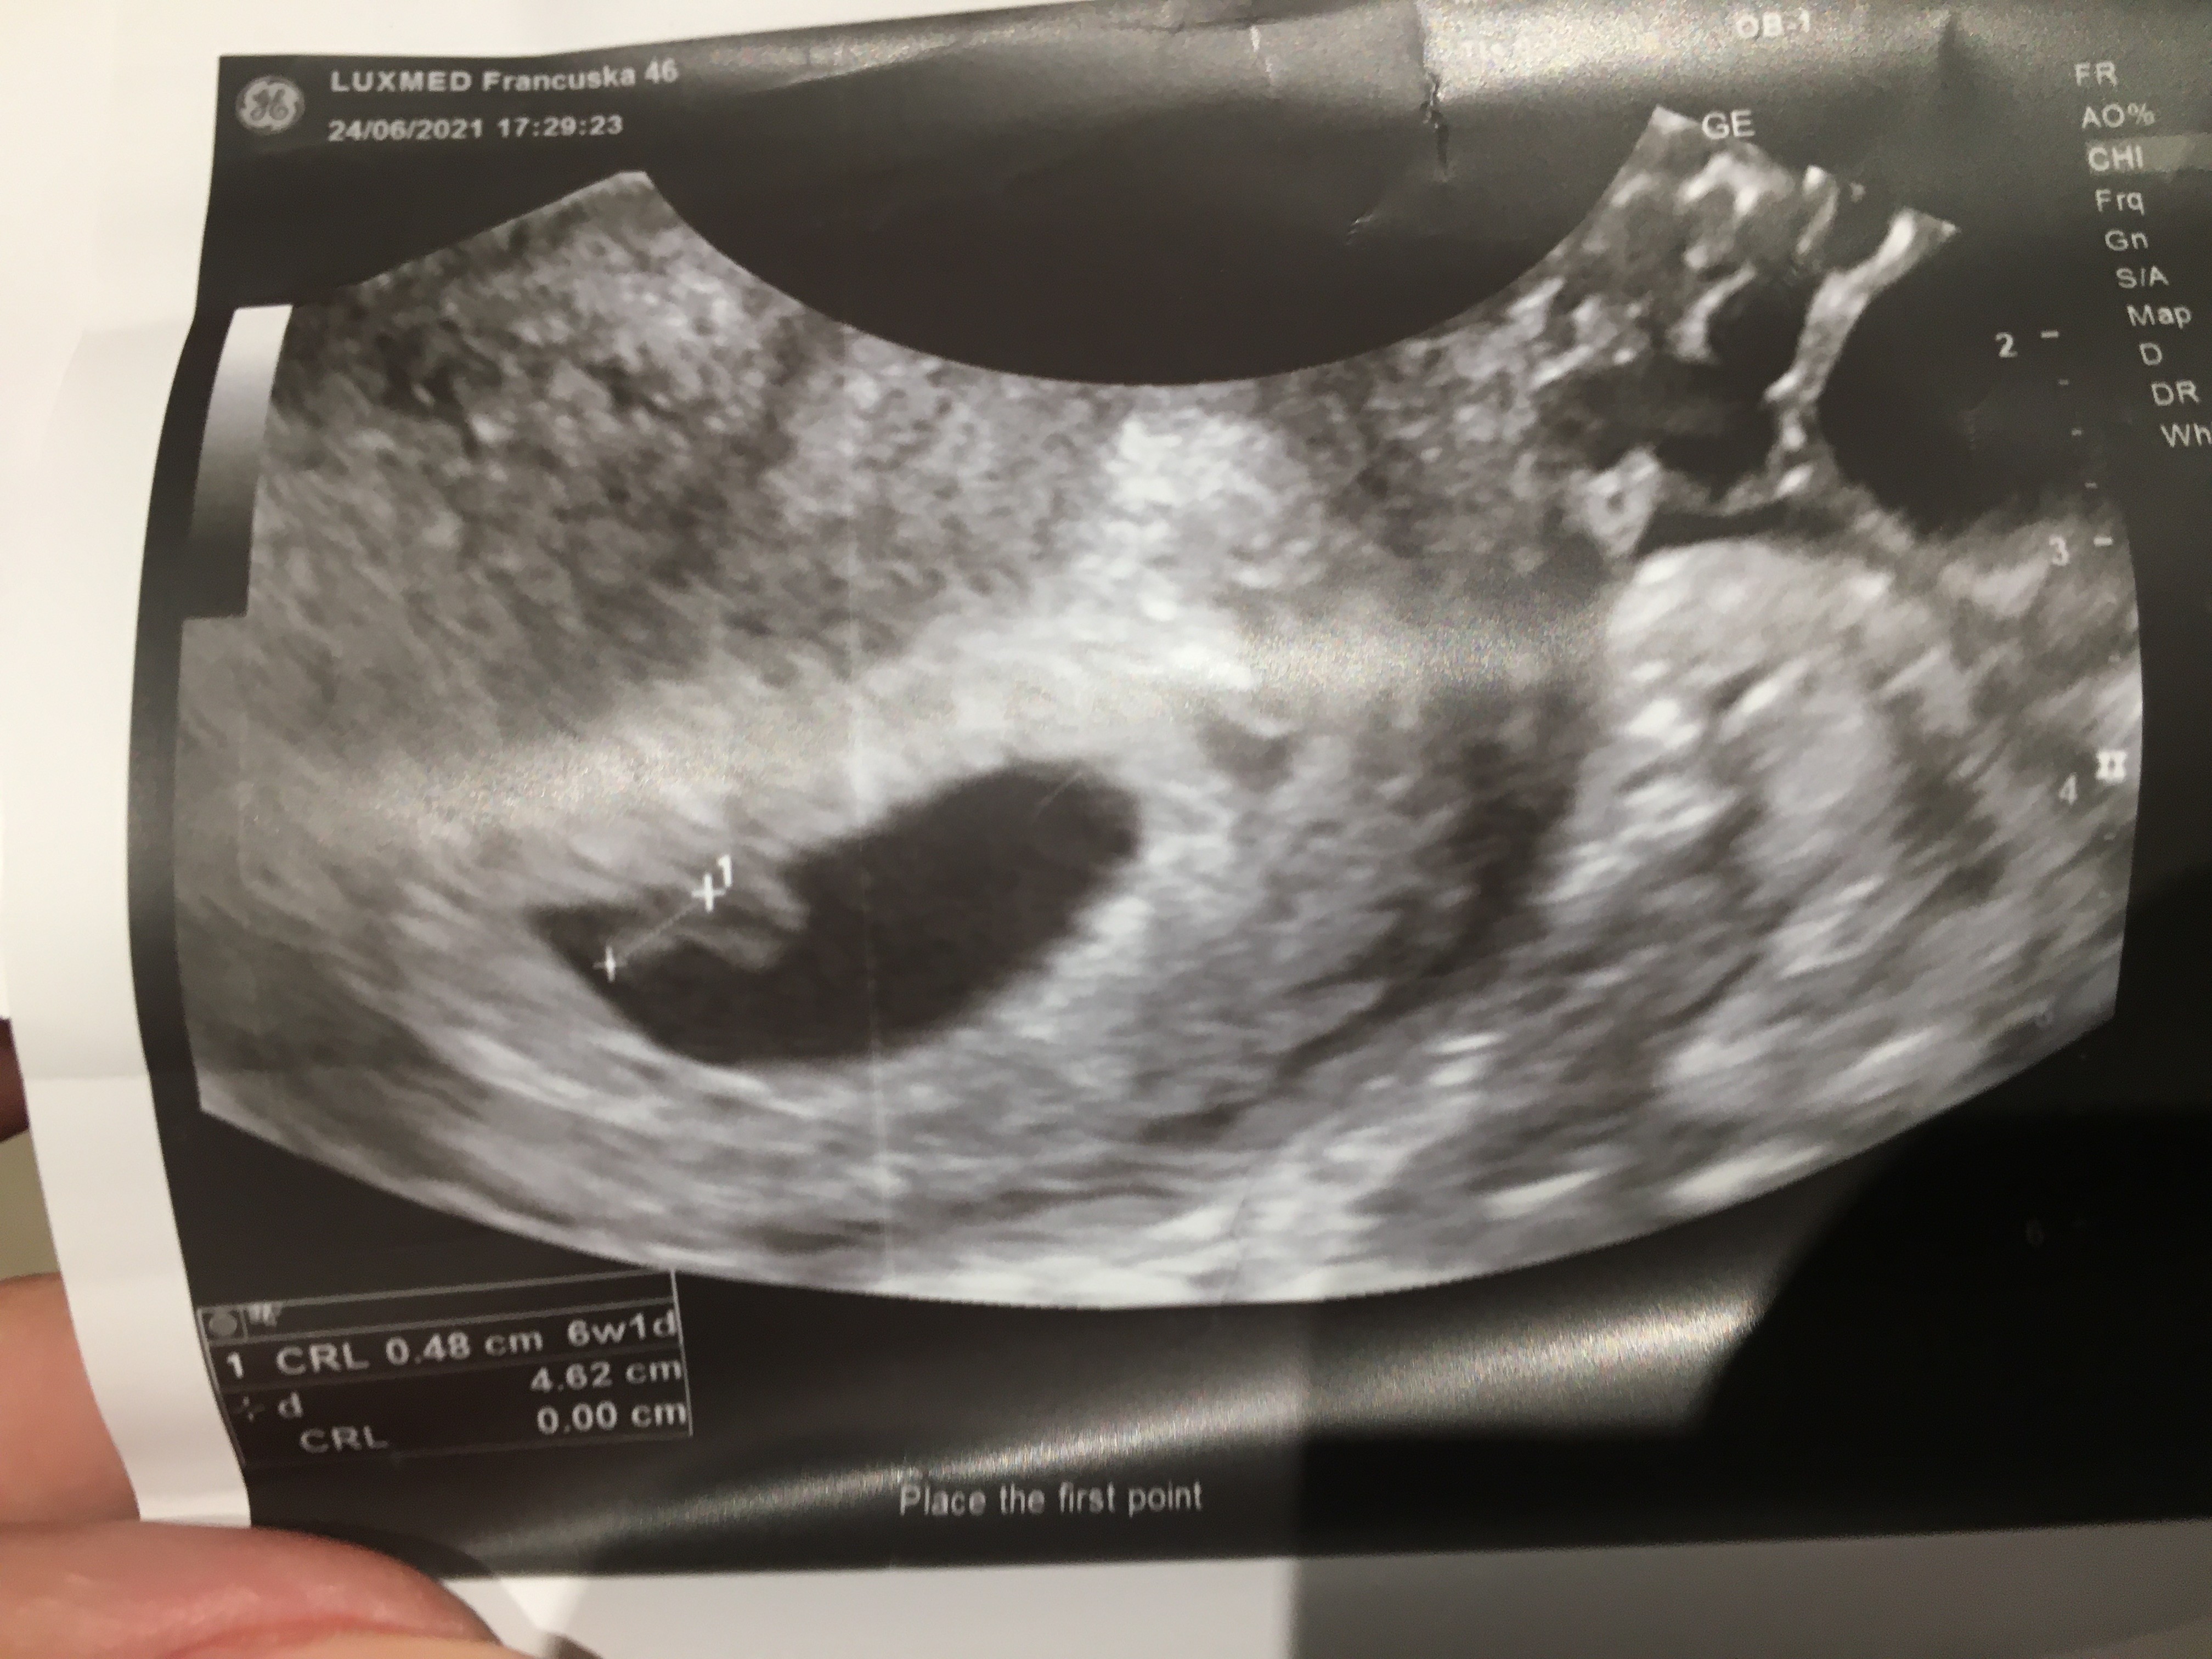

Jest mała fasolka, 0,48 cm ❤️ Serduszko bije! Wielkością na 6+1. Także warto poczekać do tego 6 tygodnia z wizytą 😁 następna za 2 tygodnie.